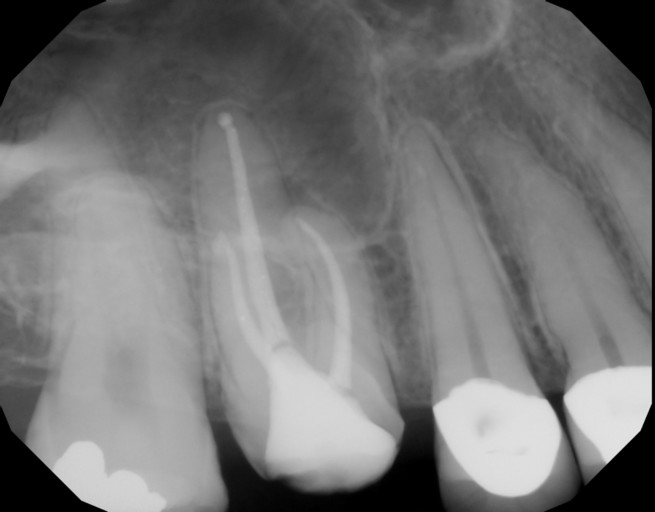

I have a question I hope you can help me with. I recently went to see my dentist because I had pain on the the left side of my mouth. It was pretty much my whole left side, top and bottom. It was very similar pain I had the year before on the right side, in which it was determined I had an infection and I needed to pull my bottom right wisdom tooth. That has since been fine. With my recent visit to my dentist with the left side she determined that I had an infection, but this time instead of pulling my one of my wisdom teeth on the left, she told me I needed a root canal on my #19 molar. I think she determined this because That tooth hurt worse than the rest and I could not eat any food with it. I ended up getting an antibiotic and within hours the pain was way less. By the next day my teeth feel perfectly normal, no pain, no sensitivity, and I can eat on that side just fine. My main concern I guess is if I really need this root canal because I do not have insurance and the procedure plus the crown afterward is very expensive. Is it possible it was just my wisdom tooth pushing on my teeth? Is it possible it was just an infection and the tooth is still alive? What would happen if I put off the root canal procedure and it turned out I really needed it, at some point would it be too late in the future to do it?